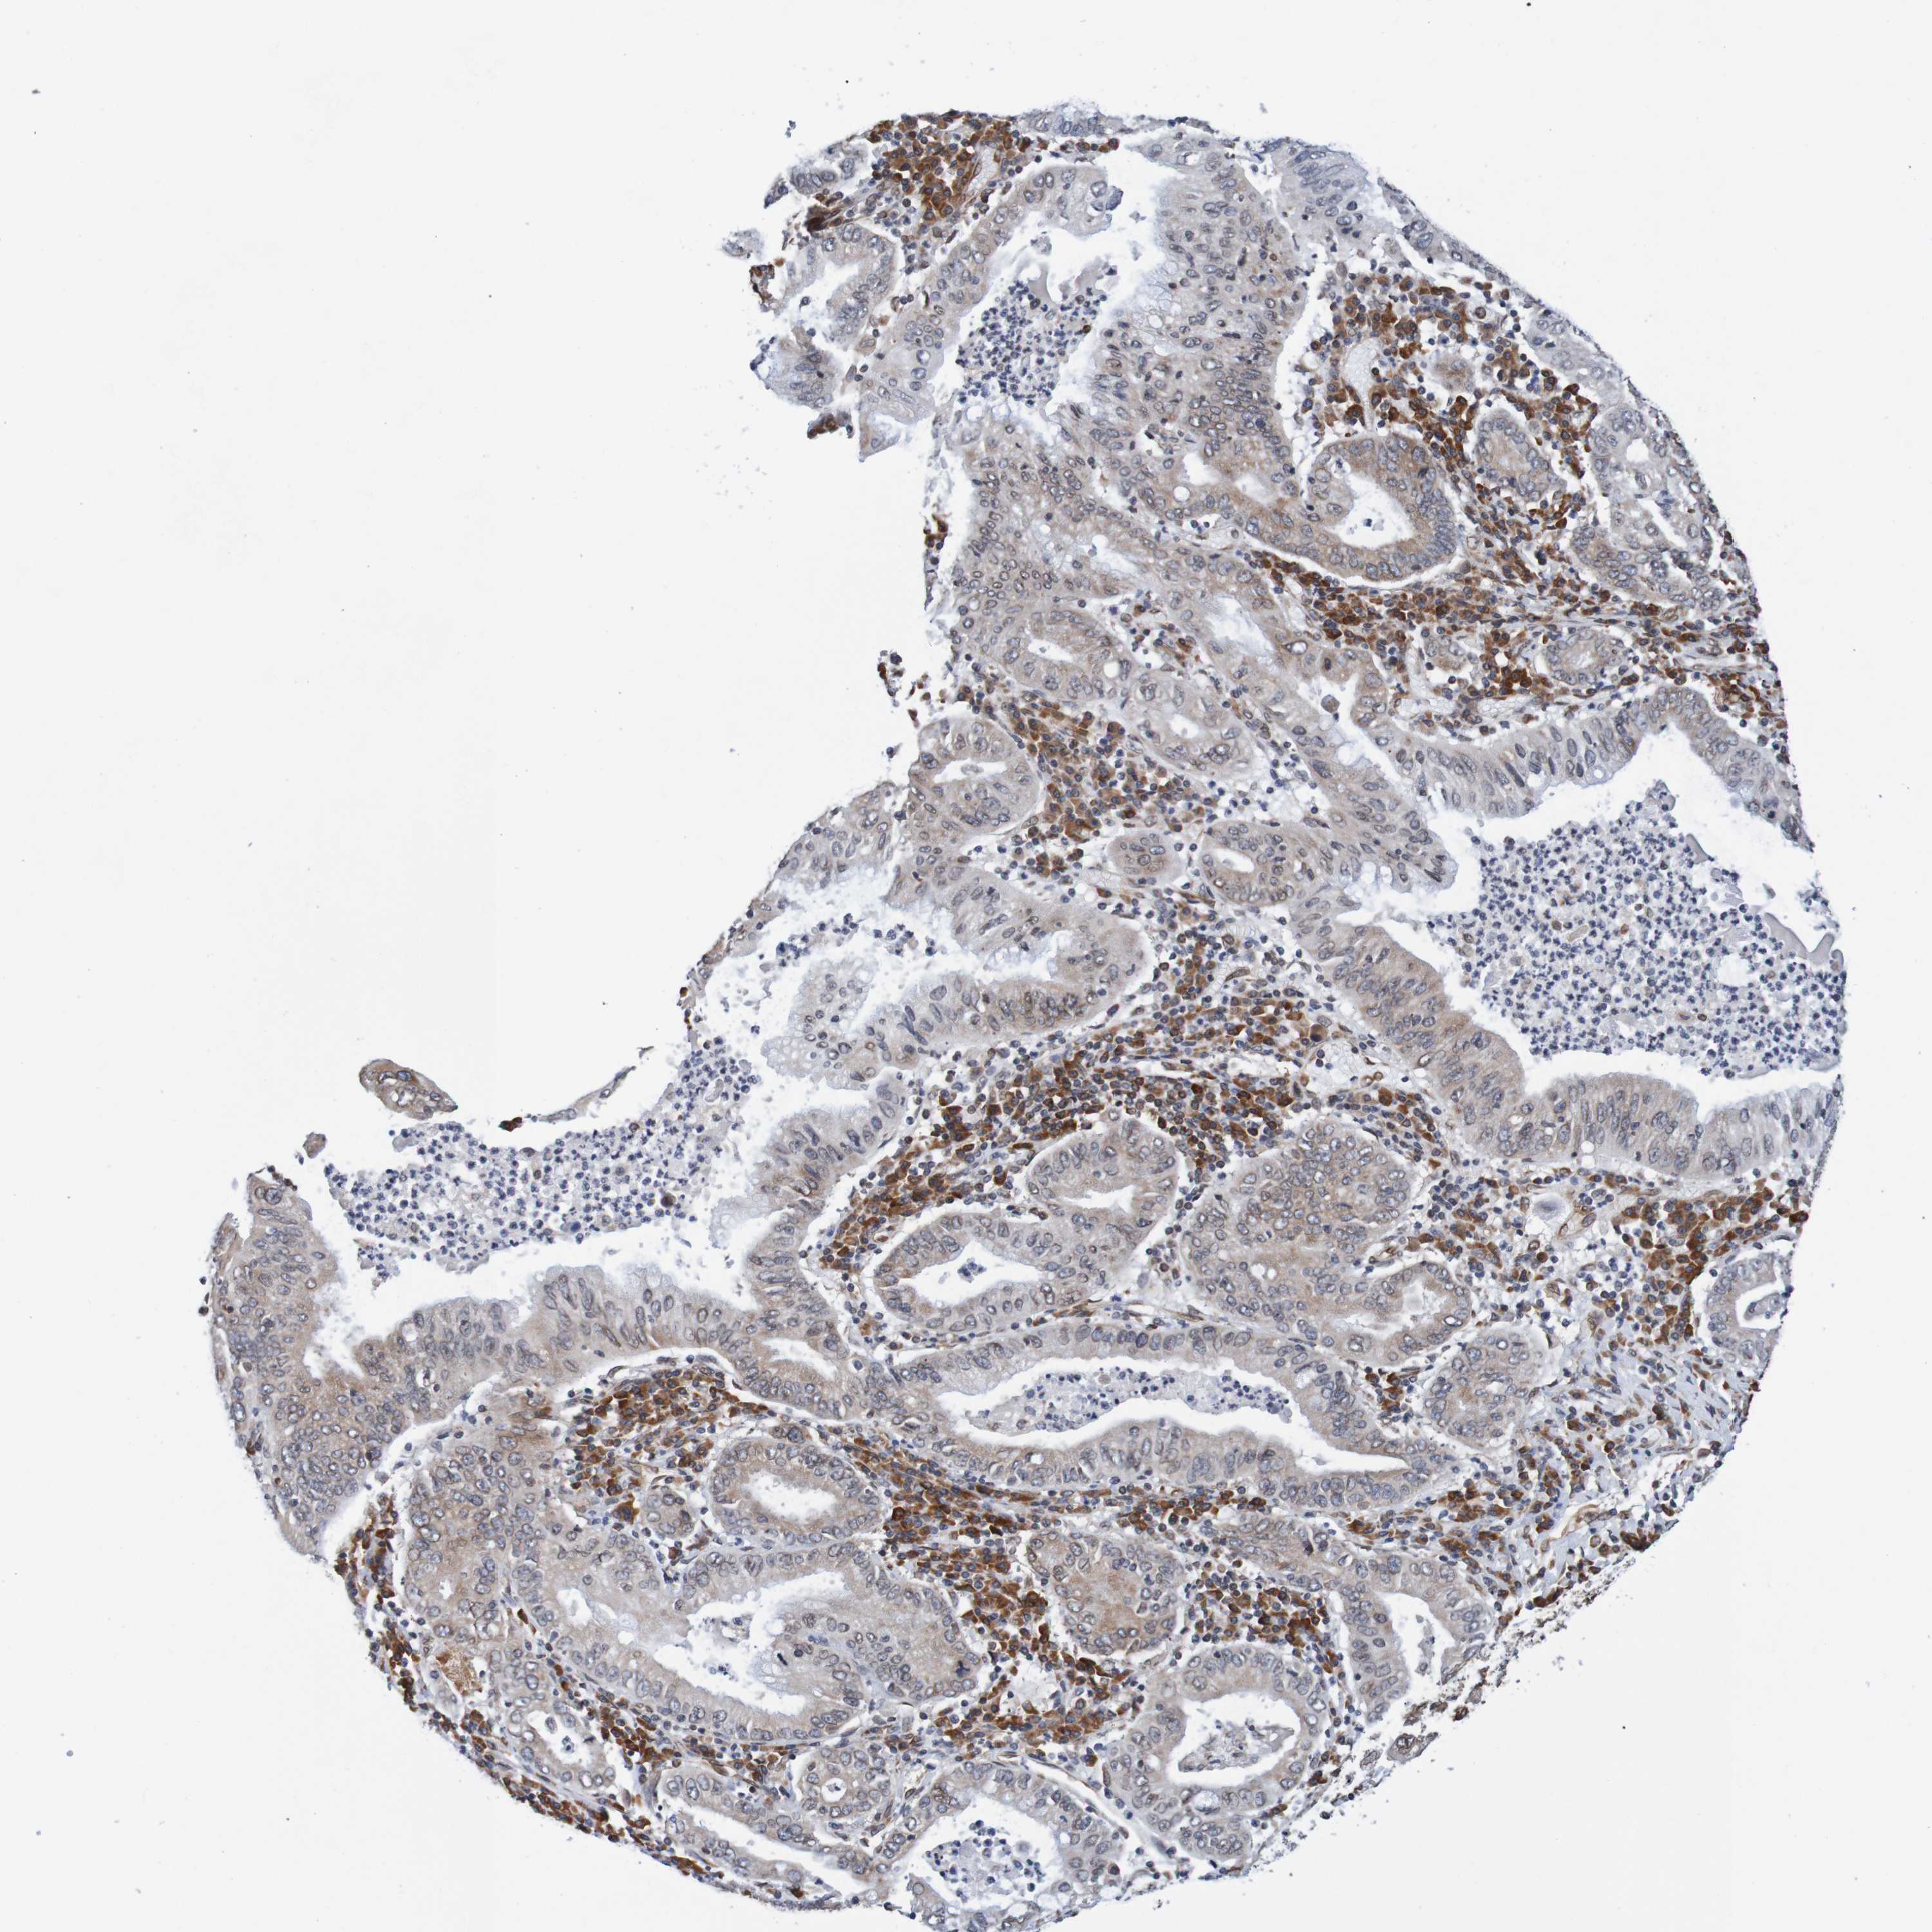

STOMACH CANCER - Protein expressioni

A mouse-over function shows sample information and annotation data. Click on an image to view it in a full screen mode. Samples can be filtered based on level of antibody staining by selecting one or several of the following categories: high, medium, low and not detected. The assay and annotation is described here.

Note that samples used for immunohistochemistry by the Human Protein Atlas do not correspond to samples in the TCGA dataset.

Antibody stainingi

Antibody staining in the annotated cell types in the current human tissue is reported as not detected, low, medium, or high, based on conventional immunohistochemistry profiling in selected tissues. This score is based on the combination of the staining intensity and fraction of stained cells.

Each image is clickable and will lead to virtual microscopy that enables deeper exploration of all samples and also displays staining intensity scores, fraction scores and subcellular localization as well as patient and tissue information for each sample.

Antibody HPA011785

Staining

High

Medium

Low

Not detected

Intensity

Strong

Moderate

Weak

Negative

Quantity

>75%

75%-25%

<25%

None

Location

Nuclear

Cytoplasmic/membranous

Cytoplasmic/membranous,nuclear

Adenocarcinoma, NOS

Adenocarcinoma, High grade